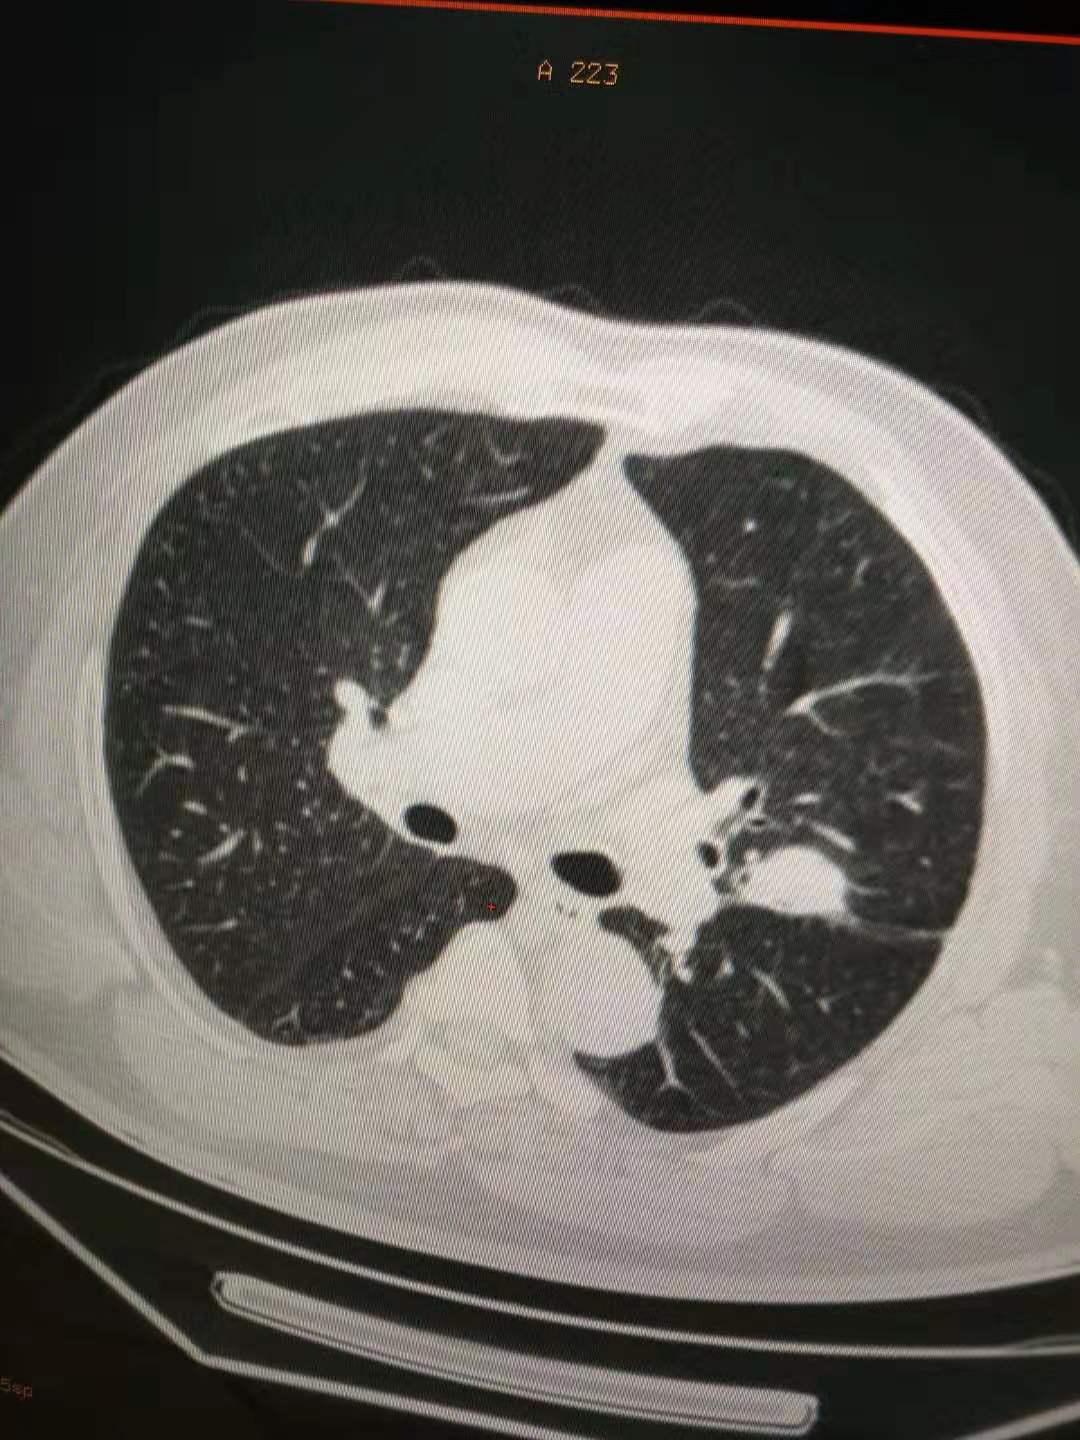

三年过去了,我的蜂疗没停过,由于没有任何症状,今年就延迟了检查,2019年11月11日,我又查了一下肺CT,医生说,那个占位不但没长,而且有钙化了,并补充了一句,你以后可以不查了!

检查结果如下:

就这个地方,还那么样!